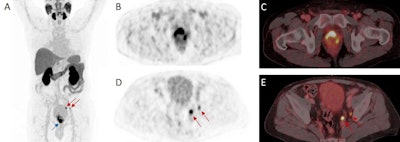

A 72-year-old patient with high-risk prostate cancer (iPSA 44 ng/mL) who underwent F-18 rhPSMA-7.3 PET/CT illustrating the primary tumor (blue arrow) and pelvic lymph node metastases (red arrows) histologically confirmed by radical prostatectomy (pT3b pN1 (2/34), Gleason score 3 + 4 = 7b); (A) maximum intensity projection (MIP), (B, C) PET, (D, E) fused PET/CT images. Image courtesy of the Journal of Nuclear Medicine.Three board-certified nuclear medicine physicians with three, six, and nine years of experience first analyzed the diagnostic contrast-enhanced CT images followed by the F-18 rhPSMA-7.3 data set at least four weeks later. Standard surgical fields were rated on a five-point scale independently for PET and for contrast-enhanced CT and results were compared with histopathological findings on a patient, right versus left, and template basis.